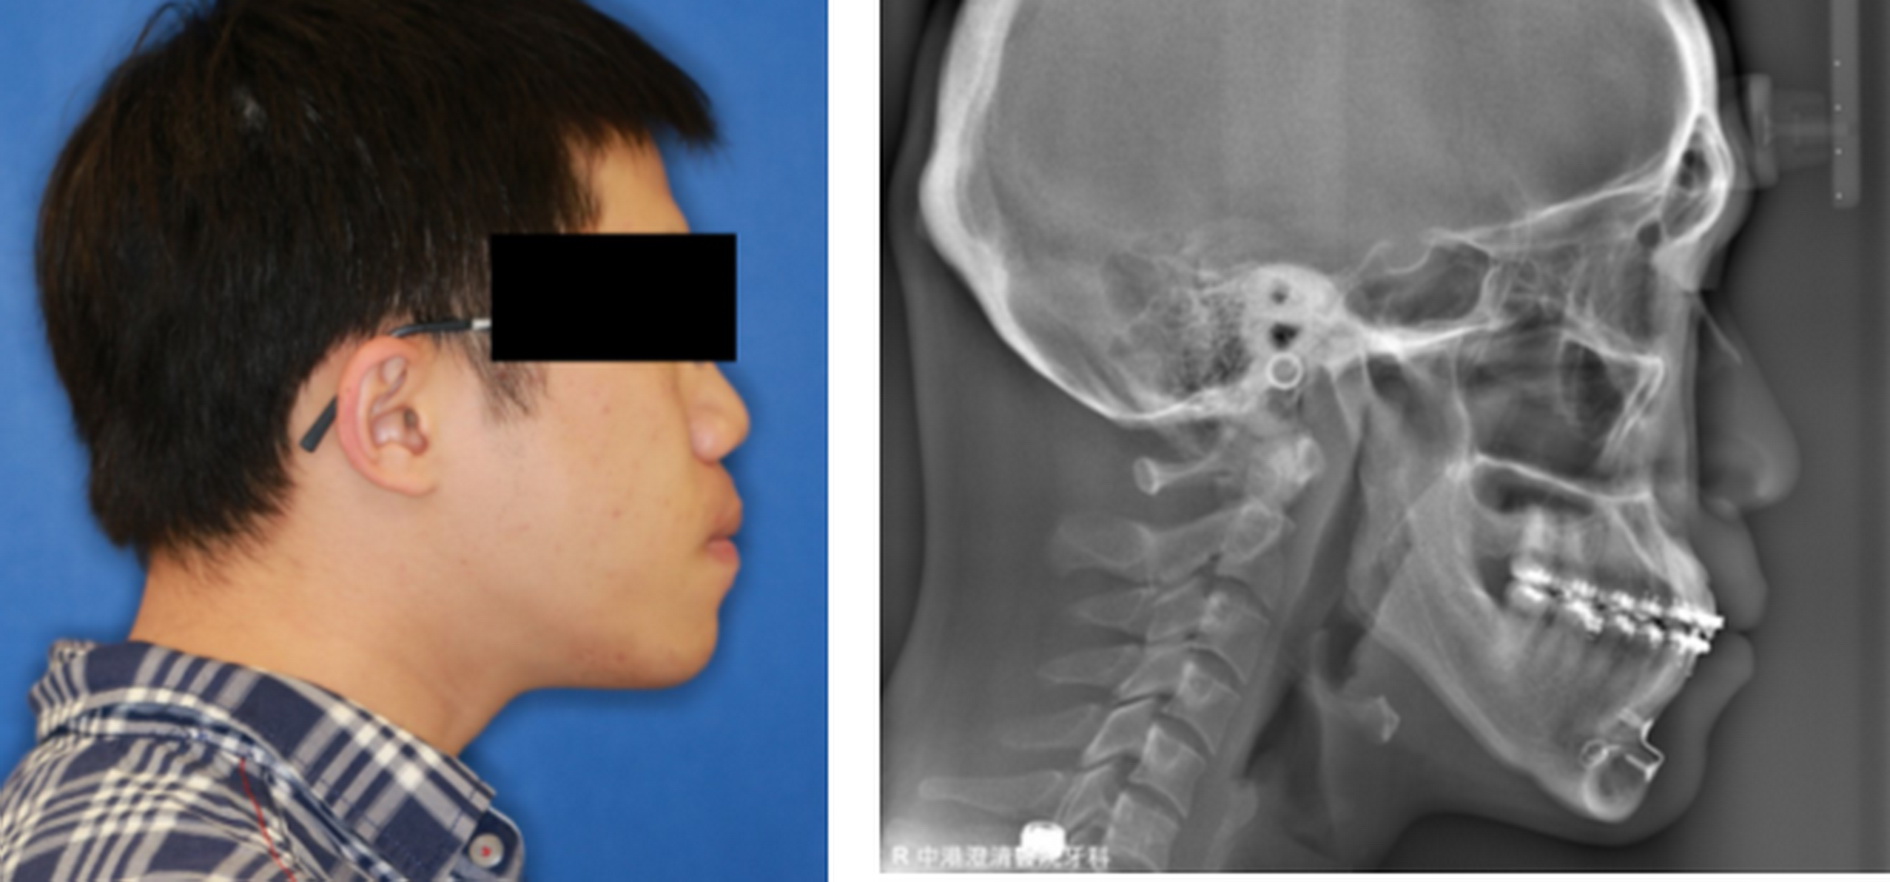

台中市1名27歲男子小時候被同學取綽號「小戽斗」,到了唸大學、出社會更影響交際生活,口罩不離口,經下顎枝垂直截骨手術後,揮別戽斗人生,變成帥哥,沒想到又逢武漢炎疫情摘不了口罩,期待疫情趕快過去,讓他展現脫口罩生活的信心。

澄清醫院中港院區口腔顎面外科主任吳伯璋說,戽斗就是下顎前突症,因下顎骨過度生長所致,最佳手術矯正的時機是在18歲以後,有助手術後的穩定性。

吳伯璋指出,下顎前突症治療採取在口腔內進行下顎枝垂直截骨手術,讓下排牙齒與上排牙齒完美密合,所謂的戽斗就消失了。手術從口腔內進行,患者顏面不留疤,成為目前主要的治療方法。下顎前突症是下顎骨過度生長所致,最好等到下顎骨完成發育穩定後再手術治療,以免因手術後因下顎骨持續成長而復發,通常18歲以上的患者,其下顎骨的成長發育已穩定。

這名男子接受下顎枝垂直截骨手術後,經6週固定下顎使骨片癒合的期間,只能用油壺從臼齒後方空隙進食流質食物,6週後,固定拆除,再進行1至2週張口訓練,要求達到4公分以上的張口度,目前已恢復正常咬合,揮別戽斗人生。